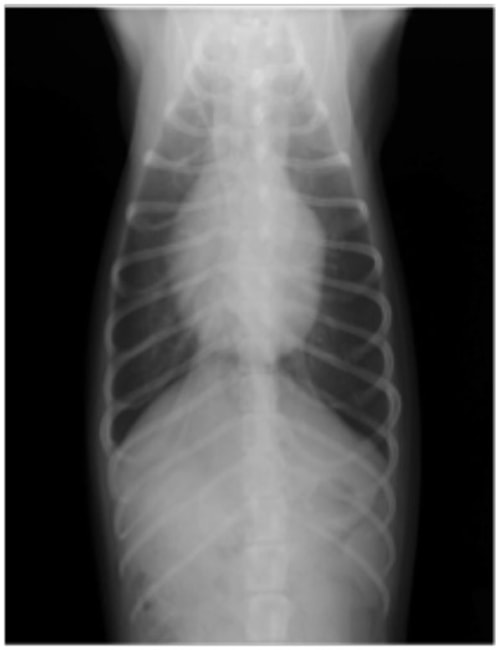

A:胸部レントゲン写真 正面像

1年ほど前より左側胸壁からLevine 3/6の心雑音が聴取されていた。雑音の精査のため、心エコー検査を行ったところ、左室流出路の狭窄を伴う肥大型心筋症(閉塞型肥大型心筋症)と判明した。心室の拡張性を上げるため、βブロッカーであるカルベジロールを用いた治療を行っている。肥大型心筋症は犬の心疾患のように、心拡大を認めないことも多く、レントゲン写真のみで心疾患の有無を判断する事が出来ない。また、閉塞を伴わない肥大型心筋症と異なり、閉塞型の本疾患の治療に対し、Caチャネルブロッカーは推奨されない。